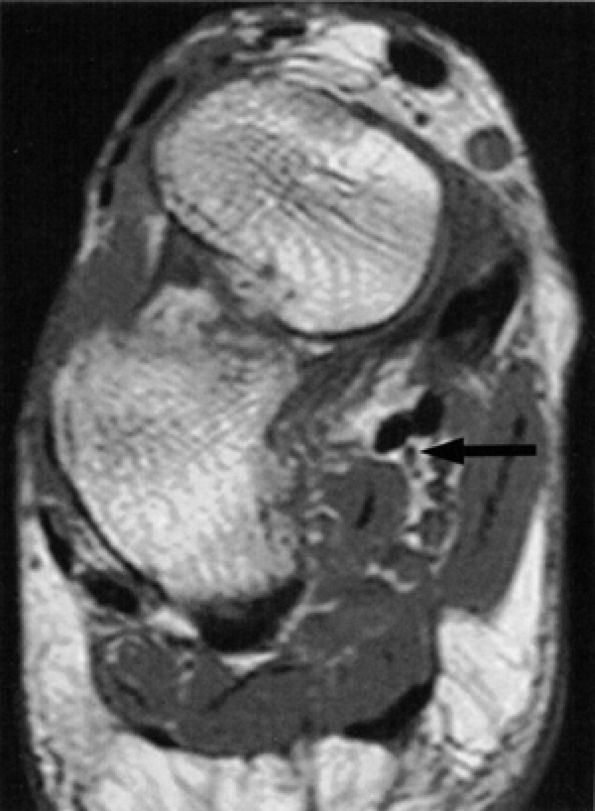

Muscle denervation edema or atrophy of the abductor hallucis and flexor digitorum brevis muscles, seen on MR images of the ankle, is compatible with medial plantar nerve entrapment (Fig. 6.52).

-

Denervation of the first lumbrical and of the flexor hallucis brevis muscle, also consistent with medial plantar nerve entrapment, is better seen on MR images of the foot (Figs. 6.53 and 6.54).

FIGURE 6.53 ● Medial plantar neuropathy. Oblique coronal (A) and axial (B) fluid-sensitive fat-suppressed images of the foot show denervation edema in the flexor digitorum brevis (arrow) and abductor hallucis (asterisk) muscles.